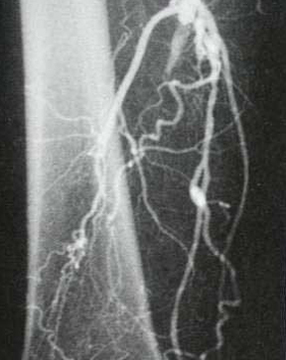

... nach Wiedereröffnung (Dilatation)